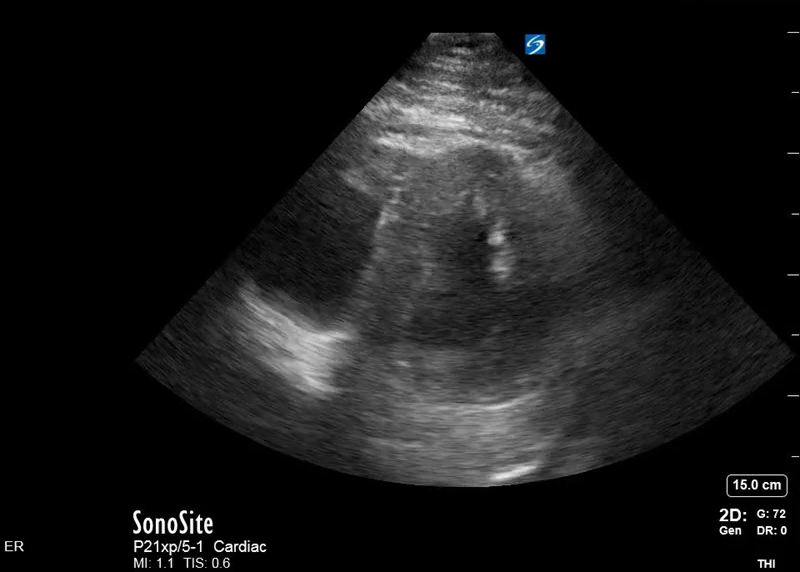

This is a parasternal short axis view in a patient with extensive pulmonary emboli on CTA. The troponin was mildly elevated and patient hemodynamically stable. A bedside echo revealed evidence of RV strain (note the ā€œDā€ shaped left ventricle). Image courtesy of: Therese Mead, DO, Emergency Physician